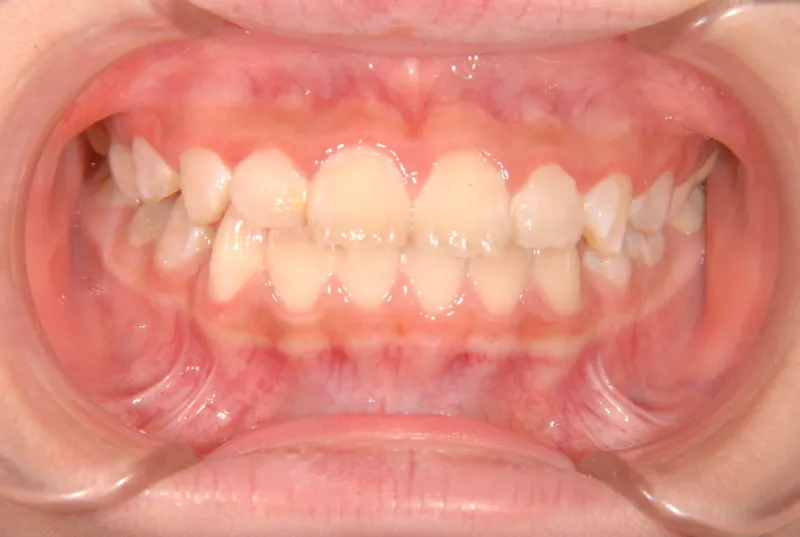

【子供の矯正(一期)】叢生・反対咬合・受け口・非抜歯症例・7歳女児【M.H様】

初診時年齢 小学校1年生 (女性) 主訴 受け口

診断名 叢生・反対咬合 装置名

受け口(下顎前突/反対咬合)

下顎が大きい傾向があります。

上下の真ん中にズレがあるのと、上下とも永久歯の生えるスペースがせまいため、オリジナル矯正装置でスペースを作り、受け口も改善していきます。

治療回数21回、2年7ヶ月の治療期間で矯正治療を終了しました。

主訴が改善され、ご満足頂きました。